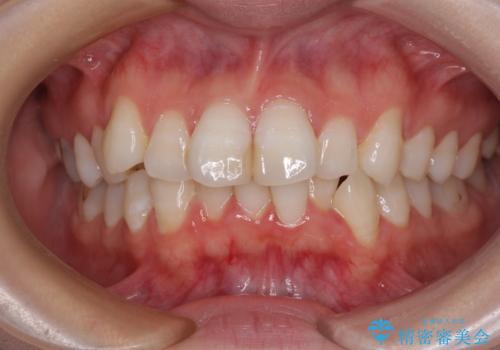

[マルチブラケットで後方移動] ワイヤー矯正で行う噛み合わせの改善